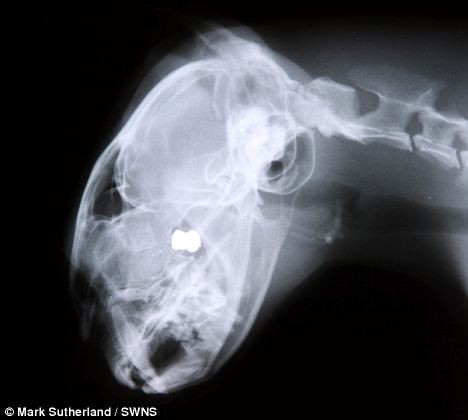

Cô Connelly, 42 tuổi, đã đưa chú mèo đến ngay bệnh viện thú y. Kết quả chụp X-quang cho biết viên đạn đã bị kẹt trong hộp sọ ở vị trí giữa hai mắt.

Trớ trêu là các bác sỹ nói rằng họ không thể mổ gắp viên đạn ra khỏi đầu chú mèo, vì như vậy sẽ gây tổn hại đến não và nó có thể bị chết.

Cookie đã thoát chết trong gang tấc khi viên đạn găm trúng giữa 2 mắt

Viên đạn găm vào não và khó có thể lấy ra được